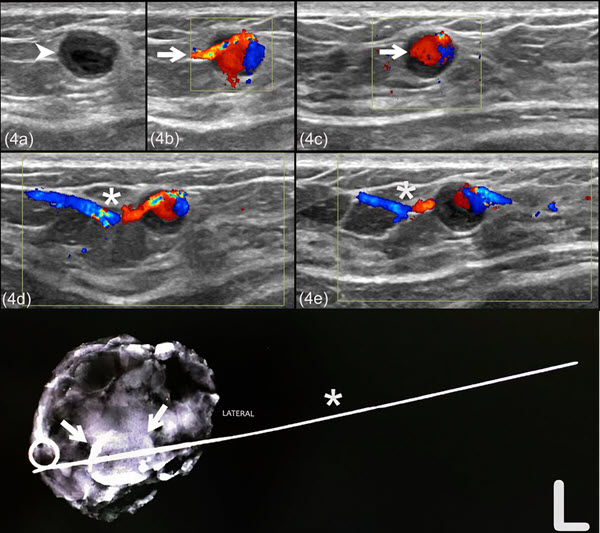

From www.radiologycases.com

Pseudoaneurysm after an ultrasoundguided breast core needle biopsy in a lactating woman Breast Ultrasound Needle Biopsy core needle biopsy (cnb) uses a hollow needle to remove pieces of breast tissue to check for cancer cells. During this breast biopsy, your radiologist uses an ultrasound machine to. It’s the standard and preferred way to. that's why doctors sometimes use an ultrasound — or a mammogram or mri, in some cases — to guide a breast. Breast Ultrasound Needle Biopsy.